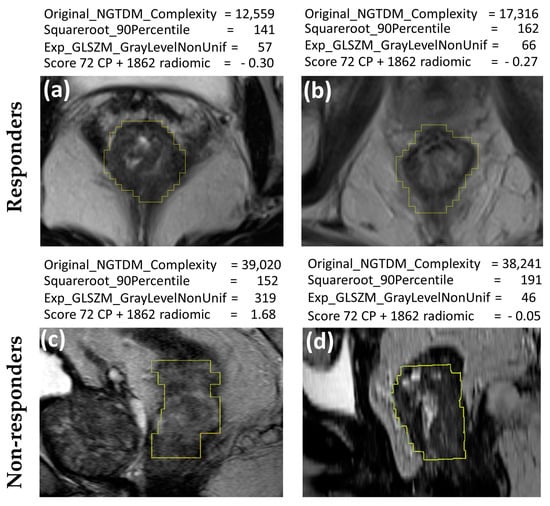

| Original_NGTDM_Complexity | Coefficient = 0.385 0.111–0.581 | p = 0.002 |

| Model: from 72 CP + 1862 radiomics features R2 = 0.47 | ||

| Mucinous histological type | Coefficient = 0.258 0.068–0.431 | p = 0.009 |

| Initial basophil count | Coefficient = 0.384 0.270–1.207 | p = 0.0014 |

| Type of CRM involvement | Coefficient = 0.319 0.071–0.542 | p = 0.008 |

| Squareroot_firstorder_90Percentile | Coefficient = 0.483 0.262–0.659 | p = 0.001 |

| Exponential_GLSZM_GrayLevelNonUniformity | Coefficient = 0.377 0.178–0.528 | p = 0.001 |